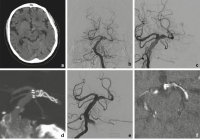

Abbildung 1a-f: Die 54-jährige Patientin erlitt bei einem Verkehrsunfall eine HWK-2-Fraktur (a, b) und eine Commotio cerebri. Das zerebrale CT zeigte in der Sylvische Fissur eine kleine umschriebene Hyperdensität (c). Angiographisch fand sich ein fusiformes Dissektionsaneurysma der rechten Arteria cerebri media (d). Das Aneurysma wurde durch zwei flusskorrigierende Stents (e, f) behandelt (p64 3,5 × 21 mm und p64 3,5 × 9 mm, Phenox, Bochum, Deutschland) und bildete sich in der Folge vollständig zurück.